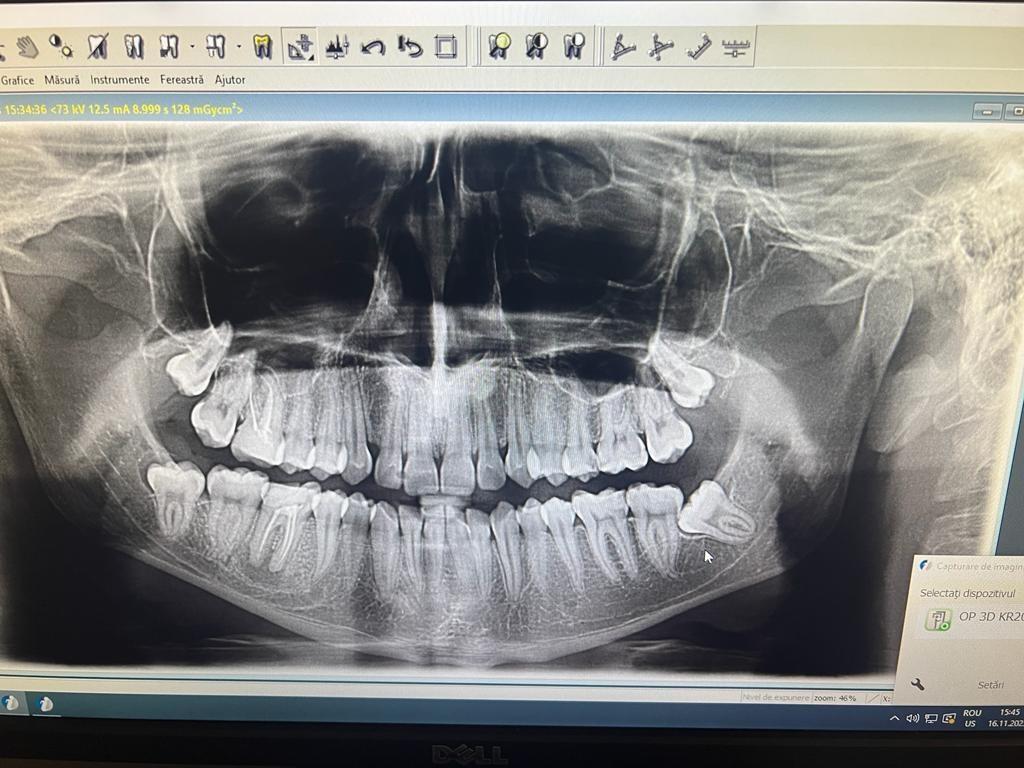

Clinica LUY ESTHETIC ART defineste parodontoza ca fiind rezultatul direct al placii dentare, care se depune pe suprafata dintilor, dar si in apropiere de marginea gingivala. Aceasta boala duce la pierderea dintilor, chiar daca ei sunt aparent sanatosi si nu prezinta carii. Edentatiile, afecteaza vorbirea, aspectul, dar si capacitatea de a mesteca.

Boala parodontala are un caracter progresiv. Pentru cazurile mai grave, recomandam tratamentul parodontal chirurgical rezectiv sau regenerativ.

Recomandam controale periodice (3-6 luni) pentru igienizari profesionale: detartraj, periaj dentar, air-flow etc. Aceste operatiuni asigura sanatatea gingiei, iar osul alveolar si ligamentele parodontale isi pastreaza integritatea.

IMPLANTOLOGIE

SUPRAPROTEZAREA PE IMPLANT